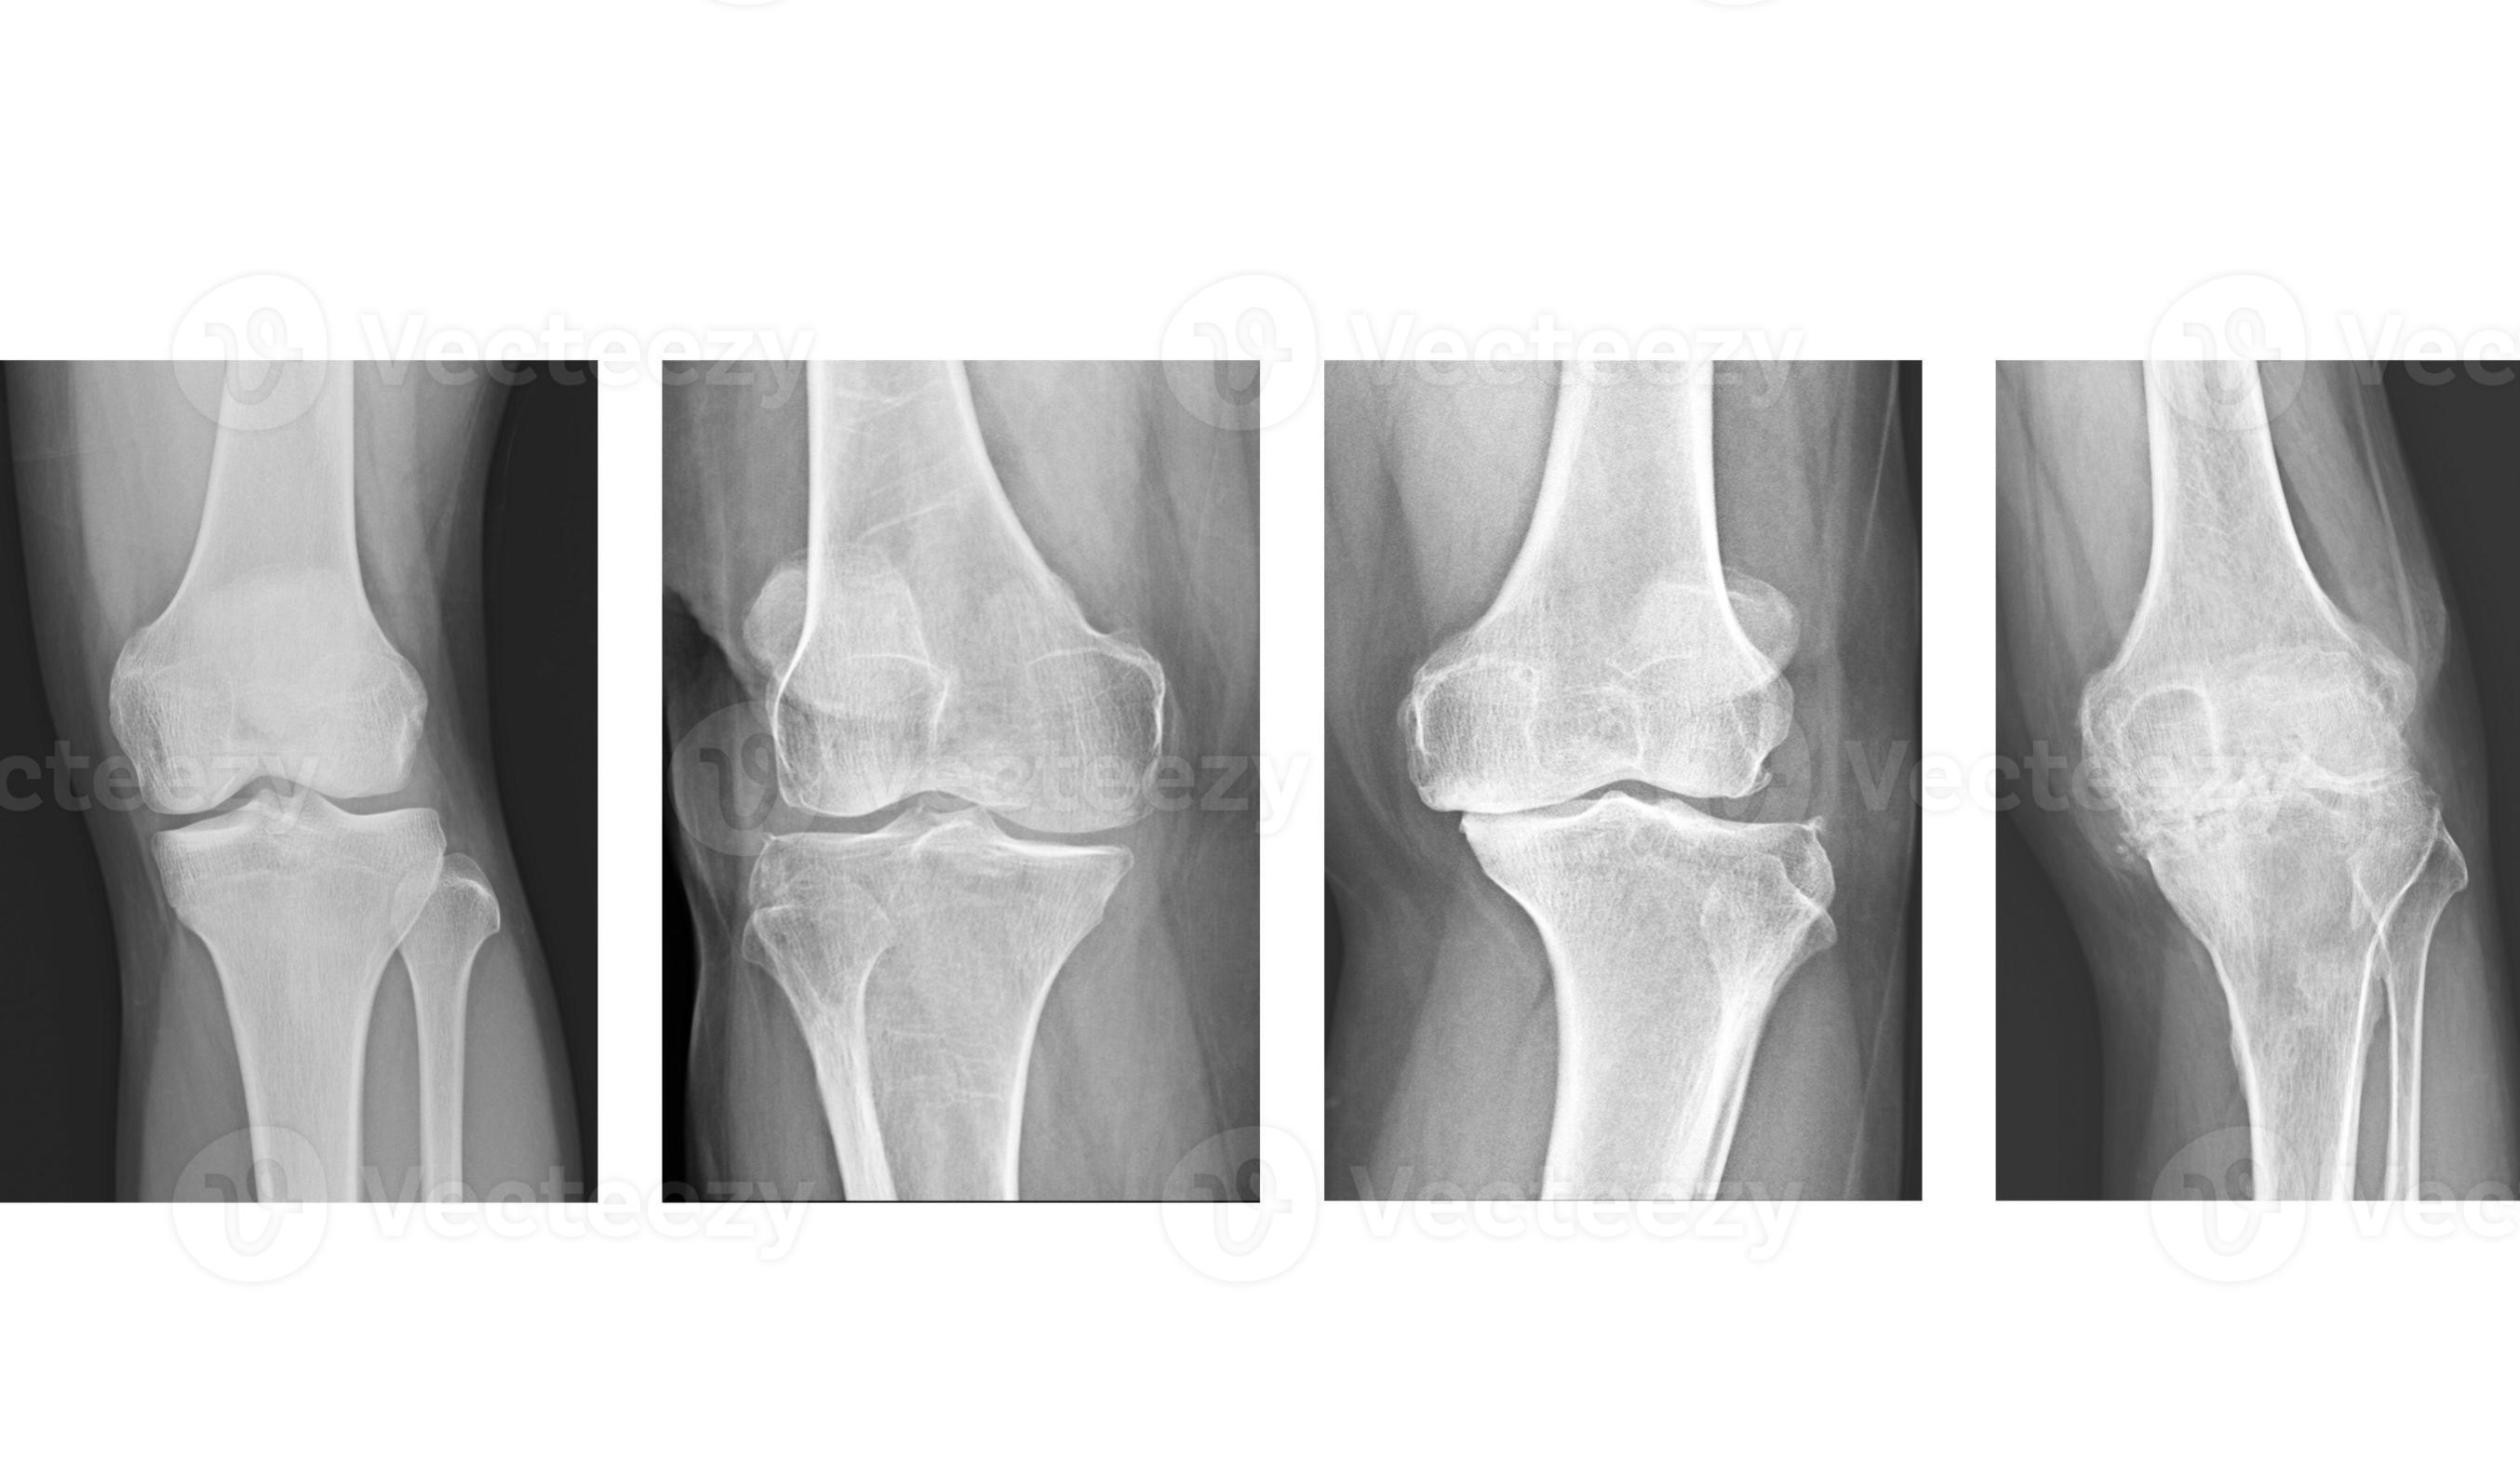

• تصویربرداری: اشعه ایکس یا MRI برای شناسایی تغییرات در وضعیت غضروف، استخوان و مایع مفصلی